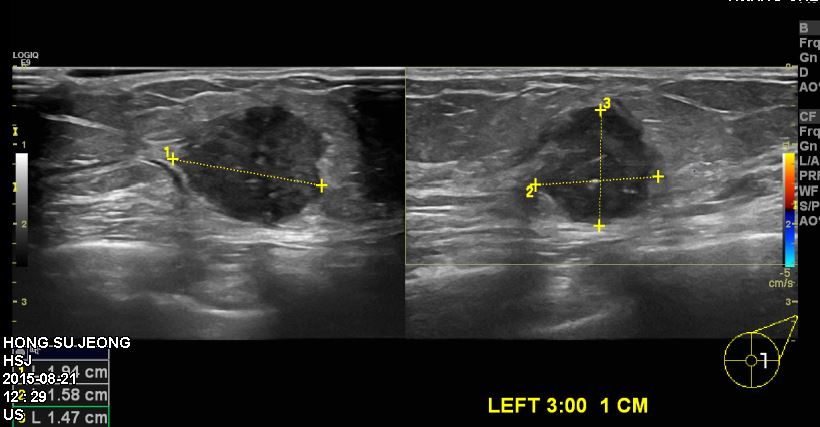

60대 여자분으로 10일전 왼쪽가슴이 뻐근하여 만져본 후 멍우리 발견되어

본원에서 왼쪽유방 3시방향 1cm떨어진위치에 조직검사시행하여

왼쪽유방침윤성유관암으로 진단되셨습니다.